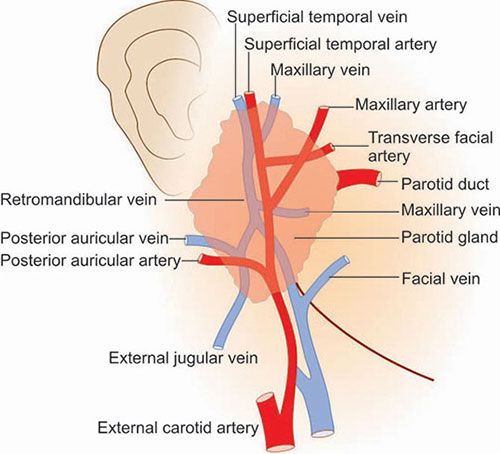

- Superficial temporal a.

- 從耳前上穿出

- ECA

- Retromandibular v.